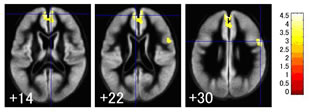

お酒をたくさん飲むと、前頭葉上部が萎縮します(数字は脳断面のレベル)黄色に見えるところが、より萎縮の進んでいるところ

収縮期血圧(値が大きい方)が高くなると、後頭葉に黄色で示した小さな場所に萎縮が見つかります。飲酒も脳萎縮の原因になっているようです。飲酒量が多い人ほど、前頭葉上部の中前頭回と呼ばれる場所に大きな萎縮が見つかります。